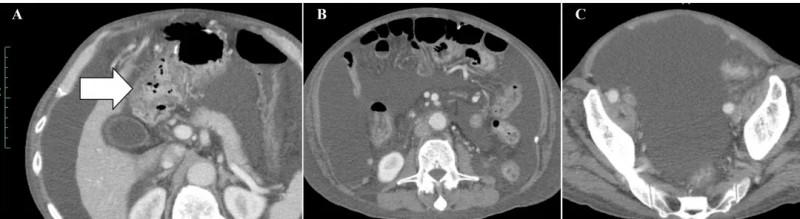

治疗效果十分显著:治疗前腹部CT可见十二指肠周围明显扩张的大网膜(详见下图A箭头所示)、大量恶性腹水(详见下图B、C)。

▲图源“Cureus”,版权归原作者所有,如无意中侵犯了知识产权,请联系我们删除